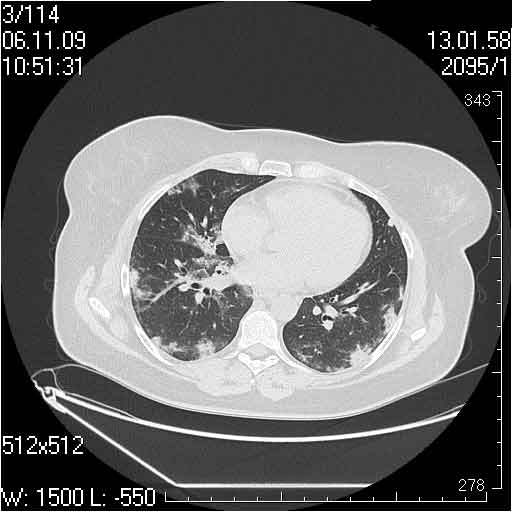

Случай №3

Женщина 51 год

Случай 3:смешанные изменения; подходят для интерстициальной пневмонии, тактика аналогична случаю 1.